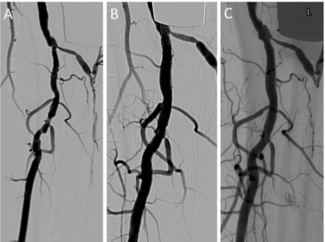

The purpose of this study was to examine the feasibility of the Navvus microcatheter coupled to the RXi system (ACIST Medical Systems) to measure lower extremity pre- and post-intervention resting and hyperemic translesional systolic pressure...